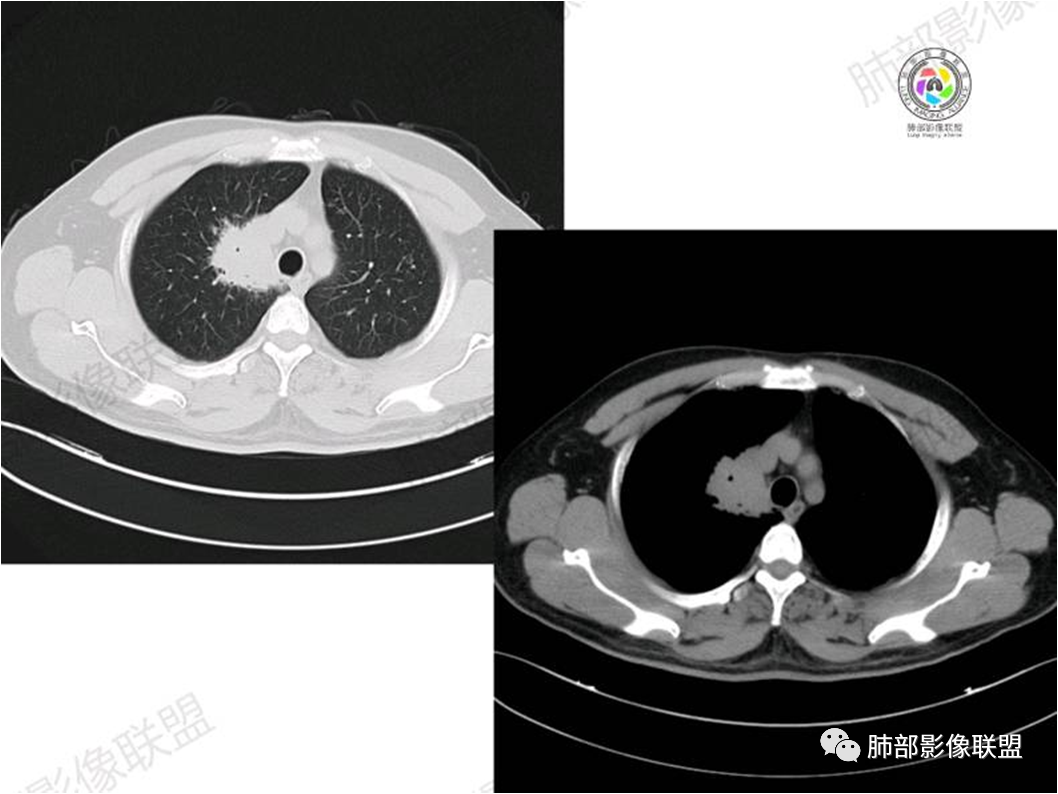

胸部CT:

中年男性,偶有咳嗽,右肺上叶近纵膈旁占位,内可见僵硬的支气管和小空泡征,病灶边缘可见分叶,毛刺,增强病灶中度以上不均匀强化,可见血管造影征,考虑恶性病变,腺癌可能性大。

中年男性,右肺上叶尖段团片病灶,密度均匀,内部支气管充气相,渐进狭窄,强化均匀,血管造影,纵隔侧未见侵犯,诊断:良性,慢性非特异性炎症/机化性炎症,IMT

右肺上叶近纵膈旁肿块,密度均匀,边缘分叶,毛刺,气管受压变窄,不均匀强化,可见血管造影征,考虑淋巴瘤,鉴别炎性假瘤。

中年男性,右肺上叶纵隔旁肿瘤,稍膨隆,有毛刺,支气管穿行,远端闭塞,强化均匀,血管走行尚可,考虑淋巴瘤可能性大(支气管远端闭塞,不太符合),鉴别腺癌(气管穿行后闭塞,不太符合),op(病灶稍膨隆)

患者中年男性,咳嗽就诊,无其他不适。胸部CT:右肺上叶尖段上纵膈旁肿块,边界清楚,边缘光滑,内见支气管受压变窄,伴阻塞性改变,增强均匀强化,见血管造影征。综合考虑恶性病变,小细胞肺癌或淋巴瘤。气管镜活检应能明确。

③扩张的充气支气管为其较特征性的表现,出现率约为89%,支气管管壁无破坏,支气管常扩张并达病灶的边缘,这与炎症性肺癌明显不同,其病理学基础是肿瘤起源于肺间质,肿瘤细胞沿着脏器解剖结构生长,周围增生的结缔组织牵拉导致支气管扩张,因而这类支气管扩张在肿瘤治疗后有时可消失;

④血管造影征是另一 点,强化的肺血管形态及走行正常,无扭曲或增 粗,其病理学基础为肿瘤细胞沿间质增生浸润,不破坏血管或支气管,病灶内肺支架结构完整,本研究发现率为75%;